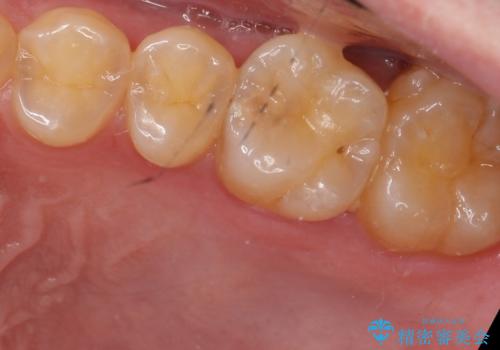

- 奥歯が虫歯になっていたため、セラミックインレーで修復しています。

治療前の写真では虫歯はわかりにくいですが、レントゲンではっきり見えます。

虫歯は外の入り口は小さいままで、中で広がっていることが多いため、要注意です。